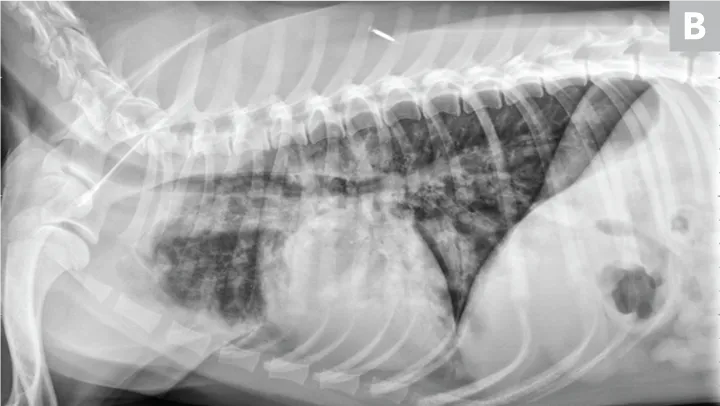

Viêm phổi cần được chẩn đoán chính xác thông qua:

-

Chụp X-quang phổi